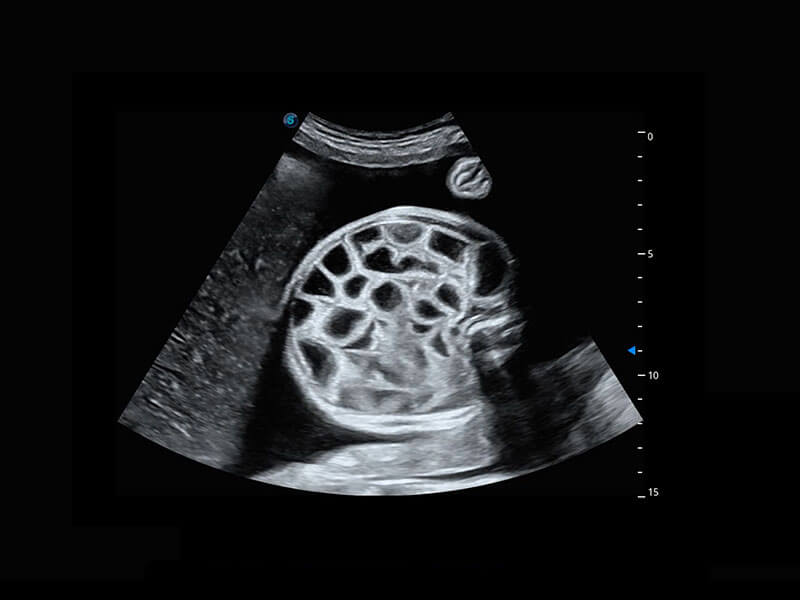

P60搭载一系列胎儿心脏成像技术,实现精细的胎儿心脏评估。

四腔切面

右室双出口

胎心容积成像